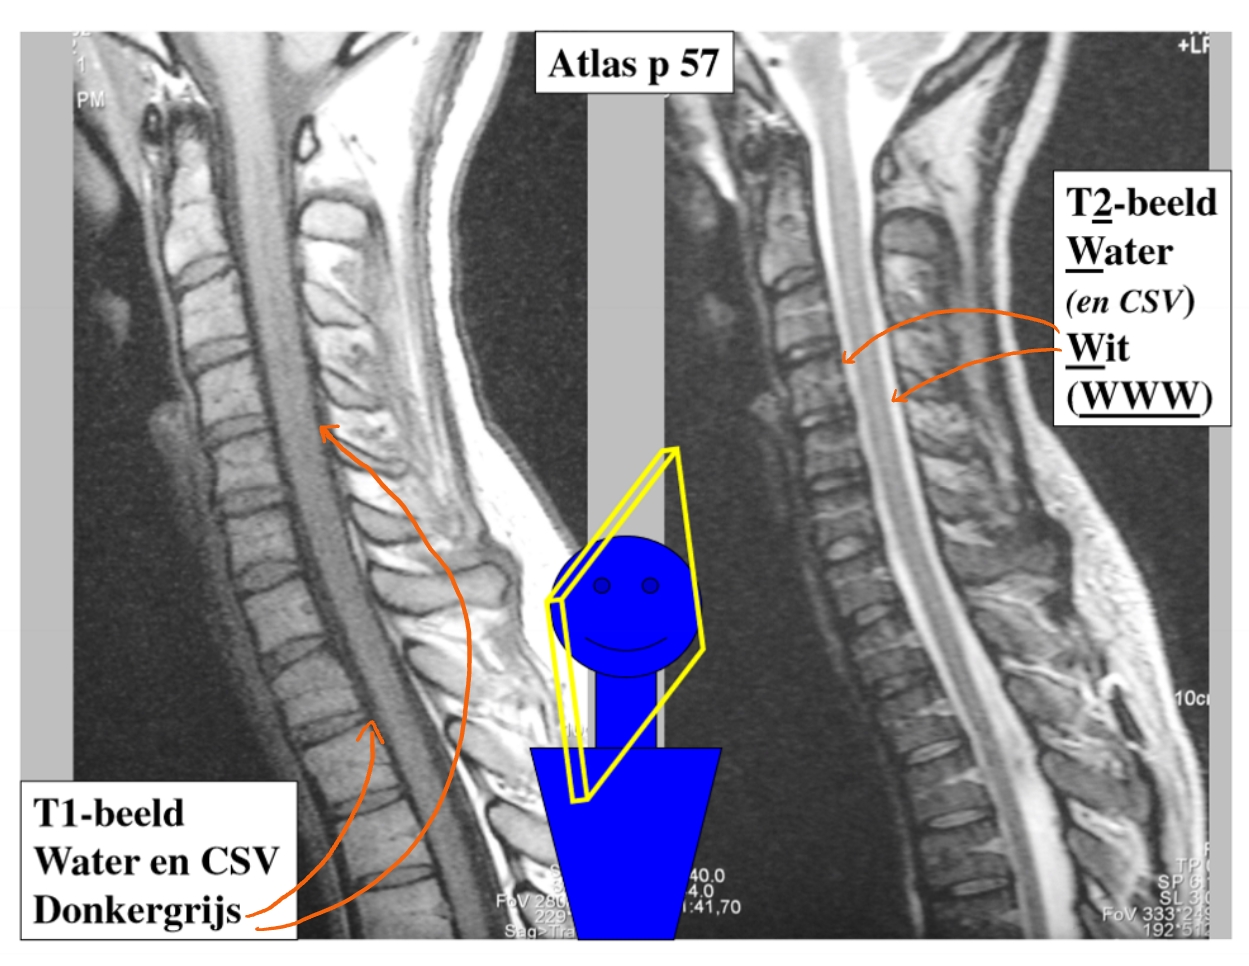

2 soorten MRI-beelden

T1-beeld

water & CSV (cerebrospinaal vocht) = donkergrijs

T2-beeld

water (en CSV) = wit

(WWW)

→ beeld in het mediosagittaal vlak

arcus anterior

arcus posterior

discus intervertebralis (= tussenwervelschijf)

embryonaal restje van de discus tussen C1 & C2

medulla spinalis

→ 1e foto = T1-beeld

→ 2e foto = T2-beeld